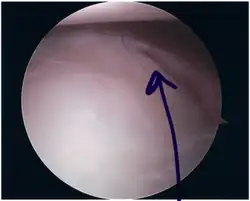

Scheur in het kraakbeen, zichtbaar tijdens een kijkoperatie -